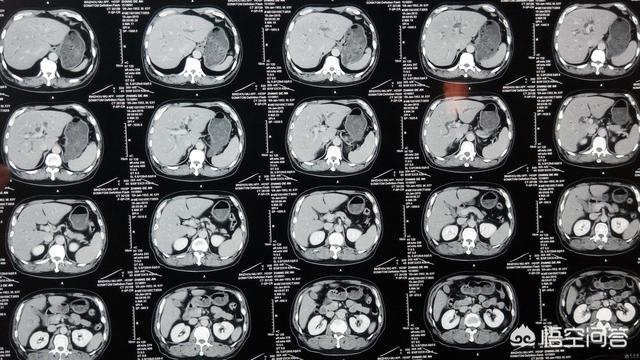

例えば、私の叔父は以前から胃痛がずっとあり、病院で全身検査も受け、消化器内科の専門医にも診てもらい、半年ほど胃の病気として治療を受けていたのですが、次第にやせやみぞおちの痛みなどの明らかな症状が現れ、病院で相談したところ、強化CTを受けるように勧められ、結局、進行した胆管がんと診断され、すでに手術の機会を失っていました。この種の悪性腫瘍の発見率は非常に低く、通常は進行した段階で発見される。 もし、ごく早い段階で強化CTが行われていれば、腫瘍はもっと前に発見され、手術のチャンスはまだあったかもしれないし、治療の価値もまだあったかもしれないし、患者は胆管がん発見から100日後に亡くなることはなかったかもしれない。

例えば、整形外科で手首の腫れを骨折と疑われた場合、骨折の有無を確認するためにフィルムを撮らなければならない。例えば、循環器科では、体調が良いという前提で心臓発作を疑い、診断を確定するために心筋酵素などの検査結果を待たなければならない。例えば、神経科では、身体症状から脳血栓症や脳梗塞を疑い、診断がつかない場合は、画像検査の結果を待たなければならない。これは診断を決定する医学的診断基準であり、医師が過剰検査と呼びたいものではありません。そのため、多くの場合、診断をさらに決定したり確定したりするための検査で診察を終わらせる必要があるのです。

第四に、現在の医療は、単に診察を受けたり、身体検査をしたりするだけで、正確な診断や治療ができるわけではないことを、議員の皆様にお伝えしたいと思います。より正確な医療を行うためには、臨床検査や画像検査が必要なのです。